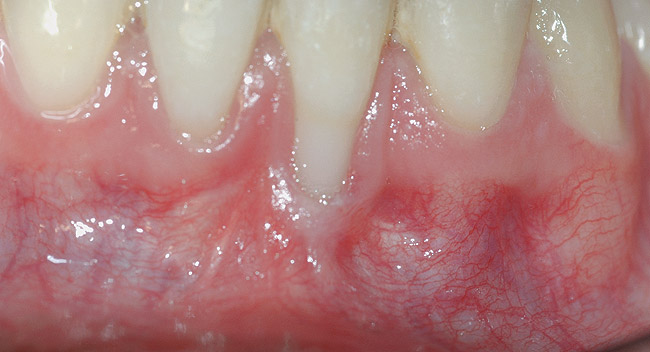

In cases with thin lingual bone, as measured on CBCT (<2.5 mm at a level of 8 mm apical to the CEJ), orthodontic treatment is not advisable, leaving surgical root coverage as the only option. However, the prognosis for this procedure is poorer, because the predominant cause is not addressed. Figure 4 shows the frontal clinical view of a patient with a hyperdivergent growth pattern who presented with post-orthodontic GR of a labially displaced lower central incisor. The sagittal CBCT view (Figure 5) shows complete absence of lingual bone, which contraindicated orthodontic tooth repositioning.

CASE 2 Fig 4. Post-orthodontic Miller Class II recession for which orthodontic treatment was not recommended. Clinical view 3 years after orthodontic treatment, showing relapse in teeth alignment and GR on lower left central incisor.

Figure 4